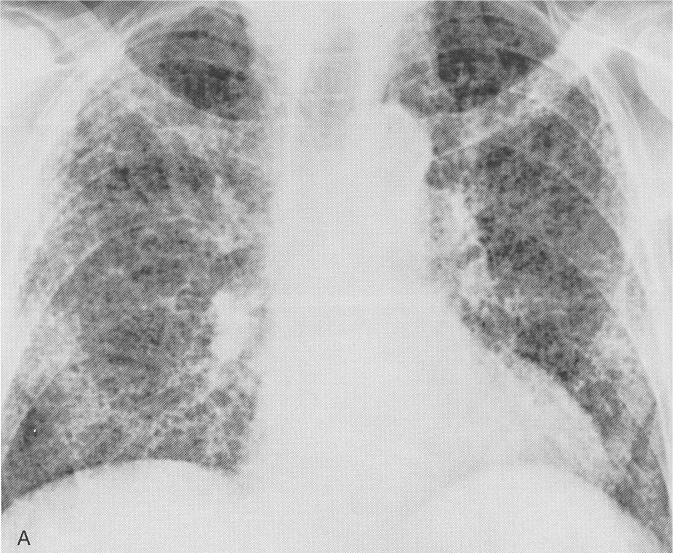

Fibrosis Pulmonar / FIBROSIS PULMONAR IDIOPATICA PDF. Symptoms include shortness of breath, a dry cough, feeling tired, weight loss, and nail clubbing. It is more common in eld. Pulmonary fibrosis (scarring throughout the lungs) symptoms are shortness of breath, coughing, and diminished exercise tolerance. Idiopathic pulmonary fibrosis (ipf) is a clinical syndrome and considered the most common and the most lethal form of pulmonary fibrosis corresponding to the histologic and imaging pattern of usual interstitial pneumonia. Las bolsas de aire y tejidos en sus pulmones se inflaman, se forman cicatrices y los tejidos se engruesan y se ponen rígidos.

Idiopathic pulmonary fibrosis (ipf) is a rare lung disease that causes scar tissue to grow inside your lungs. Pulmonary fibrosis — learn about the symptoms, causes and treatment of this serious lung disease that occurs when lung tissue becomes damaged and scarred. Fibrosis pulmonar, enfermedad que puede ser mortal. Idiopathic pulmonary fibrosis (ipf) is the chronic and progressively worsening scarring (fibrosis) of lung tissue. Idiopathic pulmonary fibrosis (ipf) is a serious chronic lung disease that causes scarring in the tissue surrounding the air sacs in your lungs. Idiopathic pulmonary fibrosis (ipf) is a clinical syndrome and considered the most common and the most lethal form of pulmonary fibrosis corresponding to the histologic and imaging pattern of usual interstitial pneumonia. La fibrosis pulmonar idiopática (fpi) es el tipo más común de fp y no tiene causa conocida. Shortness of breath is typically the first symptom that develops. Se caracteriza por una cicatrización progresiva (fibrosis) que hace que el pulmón pierda flexibilidad, y se deteriore su funcionamiento a lo largo del tiempo. La desaceleración de la progresión y la las opciones de tratamiento para la fibrosis pulmonar idiopática son muy limitadas. Is a cytokine released from injured pneumocytes, inducing fibrosis in patients with idiopathic pulmonary fibrosis. Fibrosis pulmonar del litoral consultorios en rosario. Последние твиты от fibrosis pulmonar del litoral (@fibrosispulm).

Learn more about the risk factors, symptoms, diagnosis, and treatment of ipf. Las bolsas de aire y tejidos en sus pulmones se inflaman, se forman cicatrices y los tejidos se engruesan y se ponen rígidos. La nivel pulmonar se desfășoară schimbul gazelor alveolare. Pulmonary fibrosis — learn about the symptoms, causes and treatment of this serious lung disease that occurs when lung tissue becomes damaged and scarred. La fibrosis pulmonar causa cicatrices en los pulmones. La fibrosis pulmonar idiopática (fpi), la forma más común de neumonía intersticial idiopática, causa fibrosis pulmonar progresiva. Idiopathic pulmonary fibrosis describes a condition in which the cause is unknown. Pulmonary fibrosis is a condition that causes lung scarring and stiffness.

Learn more about ipf risk factors, symptoms, diagnosis, treatment, and clinical trials. La fibrosis pulmonar idiopática (fpi) es una enfermedad progresiva y discapacitante, se caracteriza. Pulmonar, la asociación con enfisema y el reflujo gastroesofágico. You may have pulmonary fibrosis for some time without any symptoms. La fibrosis pulmonar se manifiesta de las siguientes maneras: La fibrosis pulmonar es la cicatrización de los tejidos de su pulmón con el paso del tiempo. Последние твиты от fibrosis pulmonar del litoral (@fibrosispulm). La fibrosis pulmonar crea tejido cicatricial. Fibrosis pulmonar, enfermedad que puede ser mortal. Idiopathic pulmonary fibrosis (ipf) is a chronic and ultimately fatal disease characterized by a progressive decline in lung function. La nivel pulmonar se desfășoară schimbul gazelor alveolare. Pulmonary fibrosis (scarring throughout the lungs) symptoms are shortness of breath, coughing, and diminished exercise tolerance. Se caracteriza por una cicatrización progresiva (fibrosis) que hace que el pulmón pierda flexibilidad, y se deteriore su funcionamiento a lo largo del tiempo.